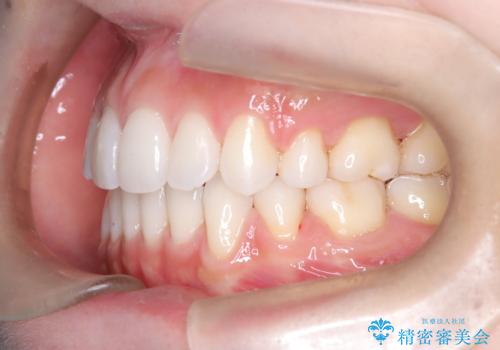

上下左右の小臼歯を抜歯後、ワイヤー矯正装置を装着し、全体のバランスを見ながら歯を移動させていきました。特に前歯の後方移動では、抜歯スペースを活かして口元を内側に下げることに重点を置きました。また、八重歯も時間をかけて丁寧に整列させ、左右の正中(真ん中の位置)もぴったりと揃えることができました。

治療期間は約2年で、歯並びだけでなく横顔の印象も大きく改善されました。治療後には「口元がすっきりして笑顔に自信が持てるようになった」とのお声をいただきました。現在は後戻りを防ぐため、保定装置(リテーナー)を使用しながら経過観察中です。ワイヤー矯正は審美性と機能性を両立できる有効な選択肢の一つです。